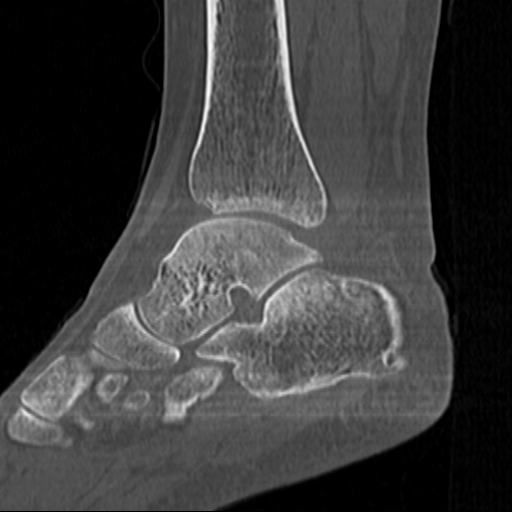

CT reconstruction provides radiologists with images for diagnosis and treatment, yet current deep learning methods are typically limited to specific anatomies and datasets, hindering generalization ability to unseen anatomies and lesions. To address this, we introduce the Multi-Organ medical image REconstruction (MORE) dataset, comprising CT scans across 9 diverse anatomies with 15 lesion types. This dataset serves two key purposes: (1) enabling robust training of deep learning models on extensive, heterogeneous data, and (2) facilitating rigorous evaluation of model generalization for CT reconstruction. We further establish a strong baseline solution that outperforms prior approaches under these challenging conditions. Our results demonstrate that: (1) a comprehensive dataset helps improve the generalization capability of models, and (2) optimization-based methods offer enhanced robustness for unseen anatomies. The MORE dataset is freely accessible under CC-BY-NC 4.0 at our project page https://more-med.github.io/